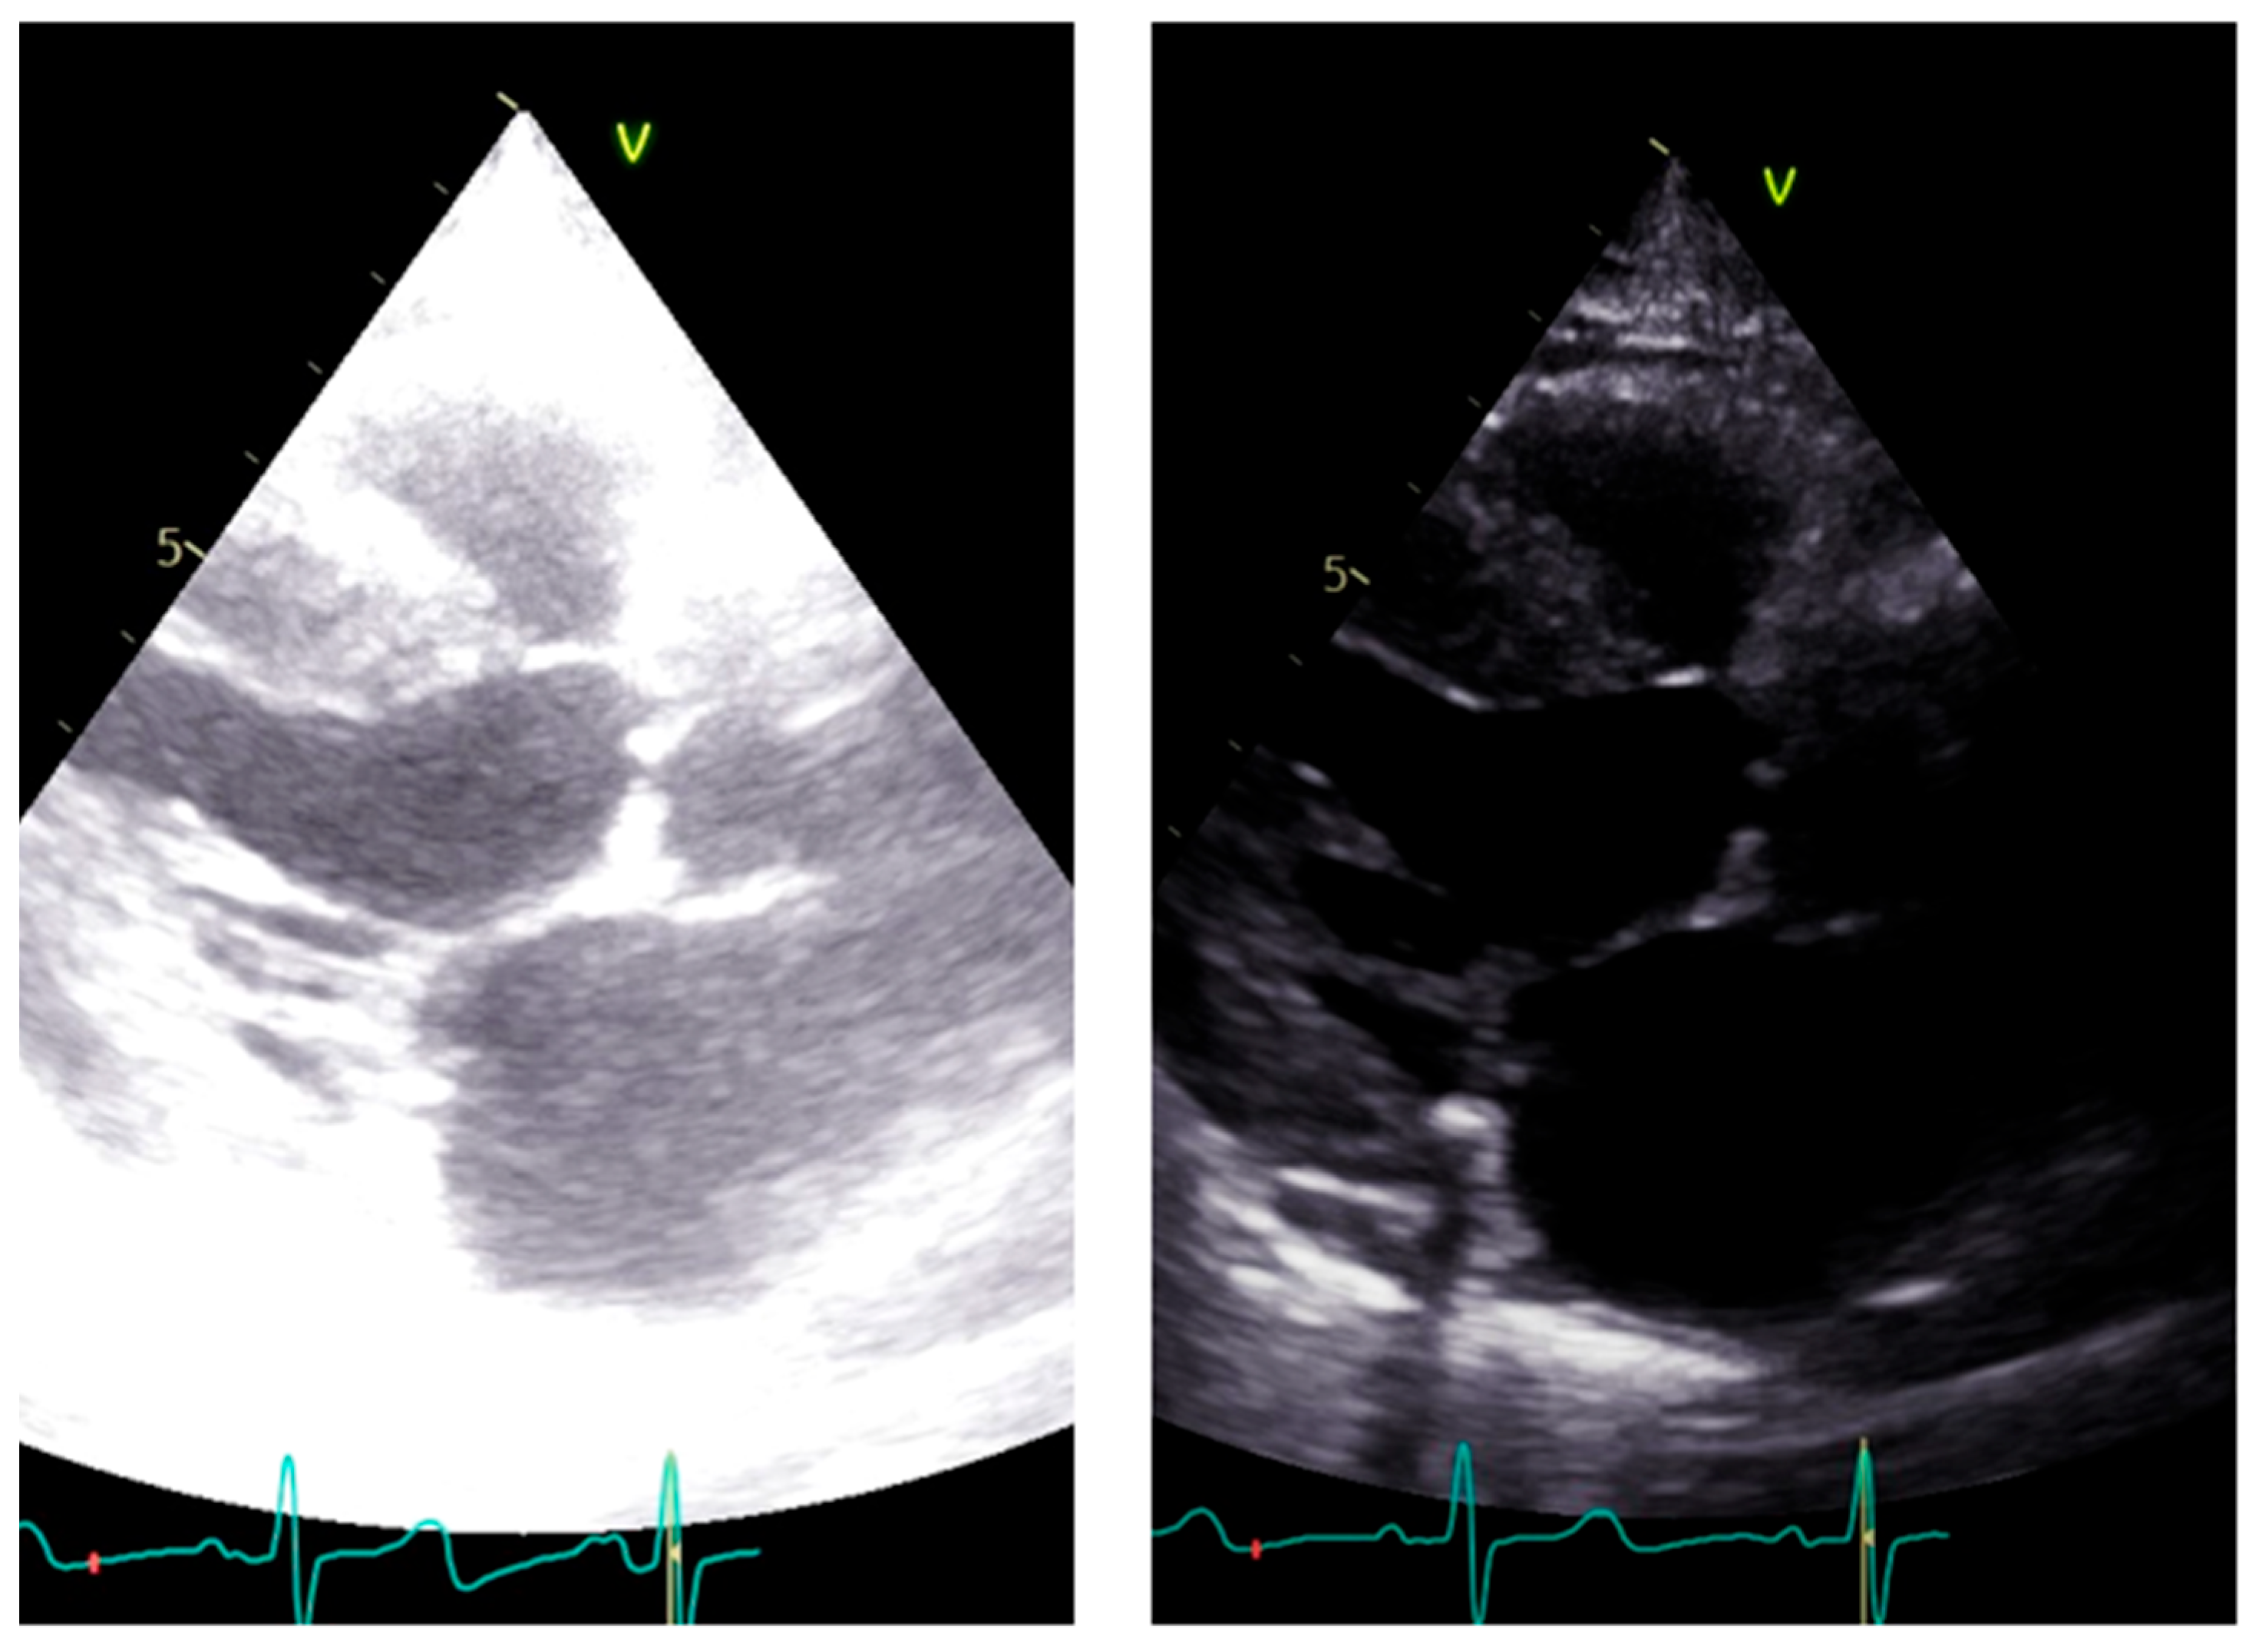

- Gain adjustment: The gain controls the amplification of the returning ultrasound signals. It is important to optimize the gain settings to achieve optimal image quality. Excessive gain can result in a bright image with noise, while insufficient gain can make the image too dark. Adjusting the gain appropriately ensures optimal visualization of cardiac structures (see later).

2. Long Axis View